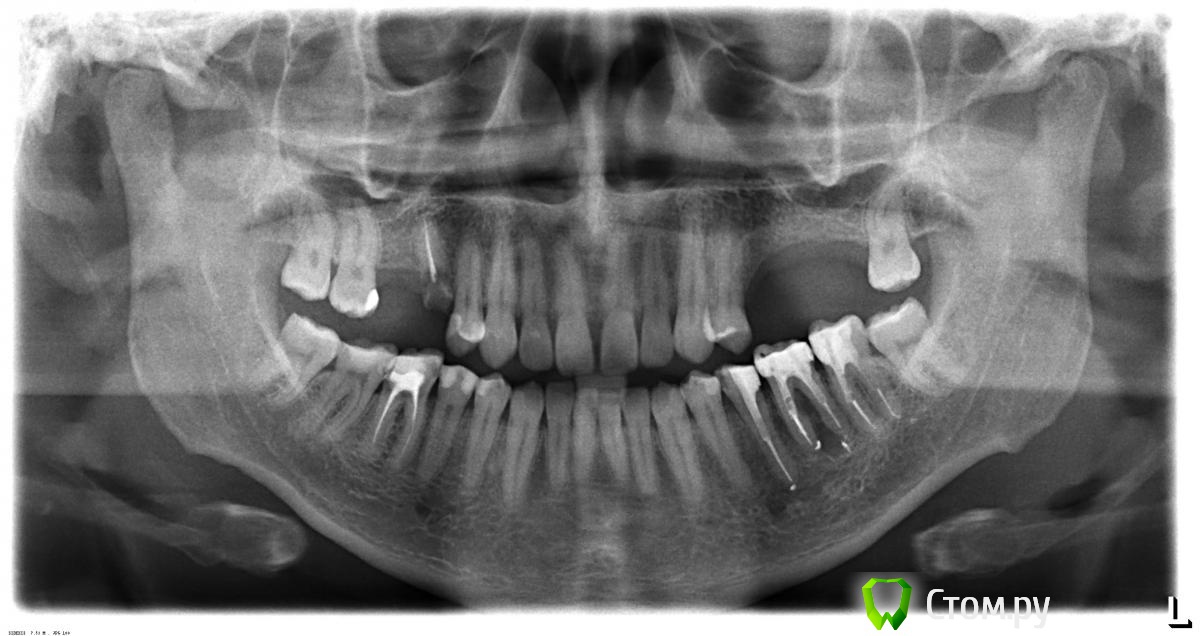

olegff Опубликовано 19 мая, 2014 Поделиться Опубликовано 19 мая, 2014 Добрый день, назрела необходимость заняться протезированием. Оптимальным видится вариант с имплантацией. Прошу проконсультировать по объему работ, снимок прилагаю. Готов "отдаться" в умелые руки знающего специалиста в Москве или области Большое спасибо! Ссылка на комментарий

sydnik Опубликовано 19 мая, 2014 Поделиться Опубликовано 19 мая, 2014 добрый день,правая сторона ---удаление 5-ки(корень) и 2 импланталевая----операция синуслифт и 3 импланта( возможно 2 ,во рту надо смотреть)сам не хирург, но думаю все эти манипуляции можно провести одномоментно и обязательно КТ Ссылка на комментарий

Bier Опубликовано 19 мая, 2014 Поделиться Опубликовано 19 мая, 2014 Внизу 46 - перелечить, 35 и 37 под коронки, 36 удалить. Можно мост, можно имплантат. В данном случае и тот и другой методы подойдут. Ссылка на комментарий

Mane Опубликовано 22 мая, 2014 Поделиться Опубликовано 22 мая, 2014 1. Удаление 15 и 362. Импланты 16,15, 25,26,27,363. Открытый синус лифтинг слева4. Возможно закрытый синус лифтинг справа. 5. Ревизия каналов 37,35,466. Восттановление культей 37,35,46 7. Протезирование и зубов 35,37,46 и имплантов коронками. Ссылка на комментарий